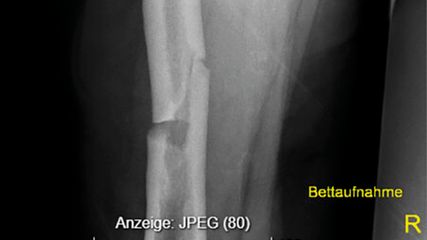

Die Hypothese der französischen Arbeitsgruppe war, dass die Mutation des UBA1-Gens eine exzessive inflammatorische Antwort durch vermehrten Zelltod verursacht. Sie prüften ihre Hypothese in einer Kohorte von 40 VEXAS-Patienten mit UBA1-Mutation. Als Vergleich dienten 24 Patienten mit schwerer autoinflammatorischer Erkrankung ohne UBA1-Mutation, 4Patienten mit MDS und 12 gesunde Patienten. Den Forschern gelang es, detailliert die biochemischen Veränderungen nachzuweisen. Unter anderem haben VEXAS-Patienten offenbar eine andere Zusammensetzung von Monozyten-Clustern und eine verringerte Anzahl bestimmter Monozyten im Vergleich zu gesunden Patienten (Abb. 1).

Abb. 1: VEXAS-Patienten zeigen eine andere Zusammensetzung von Monozyten-Clustern im Vergleich zu Gesunden, Patienten mit myelodysplastischem Syndrom (MDS) oder Patienten mit schwerer autoinflammatorischer Erkrankung ohne UBA1-Mutation (VEXAS-like) (nach Kosmider et al. 2024)1